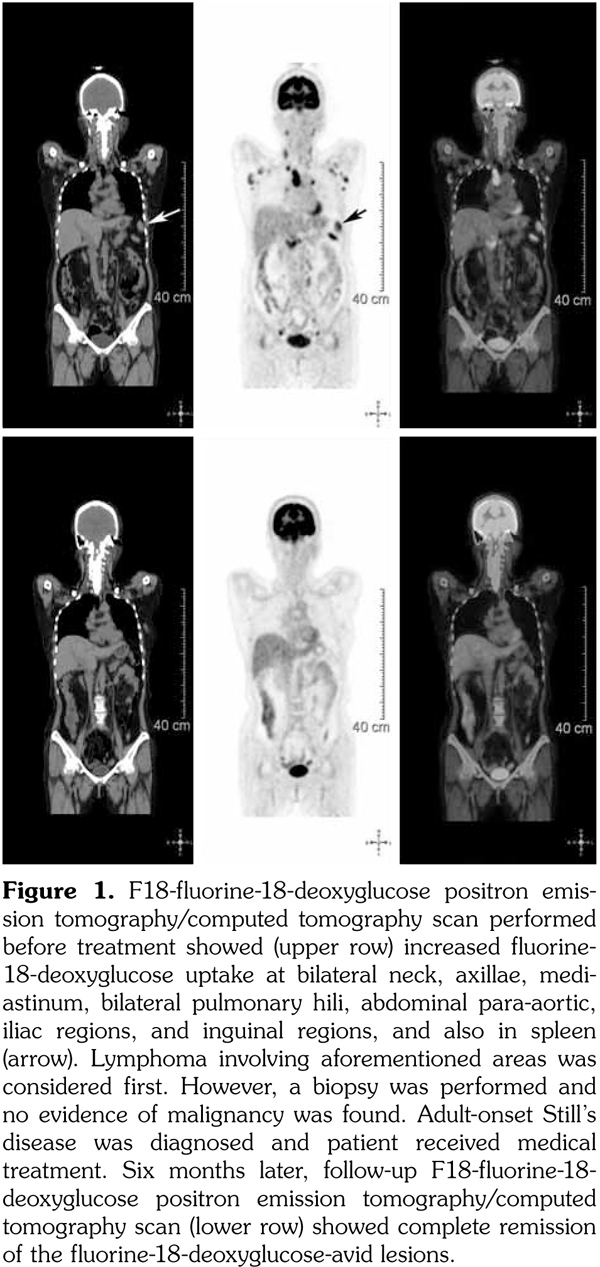

A 53-year-old female patient suffered from pain in almost her entire body, particularly the joints. Chest computed tomography revealed multiple lymphadenopathies over cervical, mediastinal, and axillary areas. A fluorine-18-deoxyglucose (FDG) positron emission tomography/computed tomography (PET/CT) revealed increased FDG uptake in many lymph nodes and the spleen. Lymphoma was suspected. However, the result of a biopsy showed no malignancy, and the gallium-67 citrate scan showed no gallium-avid tumor throughout the whole body. Adult-onset Still's disease was diagnosed and the patient responded well to steroid therapy. The follow-up PET/CT six months later showed complete remission of the FDG-avid lesions seen in the previous PET/CT. Our study suggests that FDG PET/CT combined with gallium-67 scan may be helpful in diagnosing patients with adult-onset Still’s disease. In addition, the use of FDG PET/CT alone may be useful for the evaluation of disease distribution, disease activity, and therapeutic response.

A 53-year-old female patient suffered from pain over most of her body, particularly the joints and the throat. In addition, skin rashes on the trunk without pruritus were noted. She had visited the Rheumatology, Neurology, and Orthopedic Outpatient Department several times. A chest computed tomography (CT) was performed which revealed multiple lymphadenopathies over cervical, mediastinal, and axillary areas. A positron emission tomography (PET)/CT revealed increased fluorine-18-deoxyglucose (FDG) uptake in many lymph nodes including the bilateral neck, axillae, mediastinum, bilateral pulmonary hili, abdominal paraaortic region, iliac regions, and inguinal regions as well as the bone marrow and the spleen (Figure 1). In addition, mild and diffuse increase of FDG uptake in the bone marrow was noted. Lymphoma was suspected first. After discussing with the patient, thoracoscopic mediastinal lymph node biopsy was performed. Fifteen lymph nodes were taken and the results showed histiocytic infiltration in sinusoid area and anthracotic pigment deposition. Reactive lymphoid follicle hyperplasia and focal fibrocalcified nodule formation were also noted. No tumor cell was seen. Gallium-67 (Ga-67) scan was conducted and no gallium-avid tumor was seen throughout the whole body (Figure 2). The laboratory data were negative for antinuclear antibodies, rheumatoid factor- immunoglobulin M, and extractable nuclear antibody, while alanine aminotransferase was high. The final diagnosis was AOSD. In our case, there were no symptoms or signs of either high fever or debilitating joint although the FDG PET showed multiple FDG-avid lesions in the whole body scan. According to the experience of our rheumatologists, methylprednisolone (Metisone) 4 mg/day and non-steroidal anti-inflammatory drugs were prescribed initially and the response to treatment was good. Six months later, the follow- up PET/CT showed complete remission of the FDG-avid lesions seen in the previous PET/CT (Figure 1) and the patient’s symptoms relieved. A written informed consent was obtained from the patient.

In this study, we present the FDG PET/CT and Ga-67 scan findings of a patient who met the Yamaguchi classification criteria for AOSD. The FDG PET/CT scan was not helpful in diagnosing AOSD in this case since lymphoma could not be ruled out. However, the FDG PET/CT scan results were useful for evaluating the distribution and severity of the disease. A negative Ga-67 scan could be beneficial as it would exclude lymphoma. After the diagnosis of AOSD was established, the patient received nonsteroidal anti-inflammatory drugs and glucocorticoids with a good response. Disease activity and therapeutic response were monitored by FDG PET/CT and the findings of a scan performed six months after treatment were negative.(13)